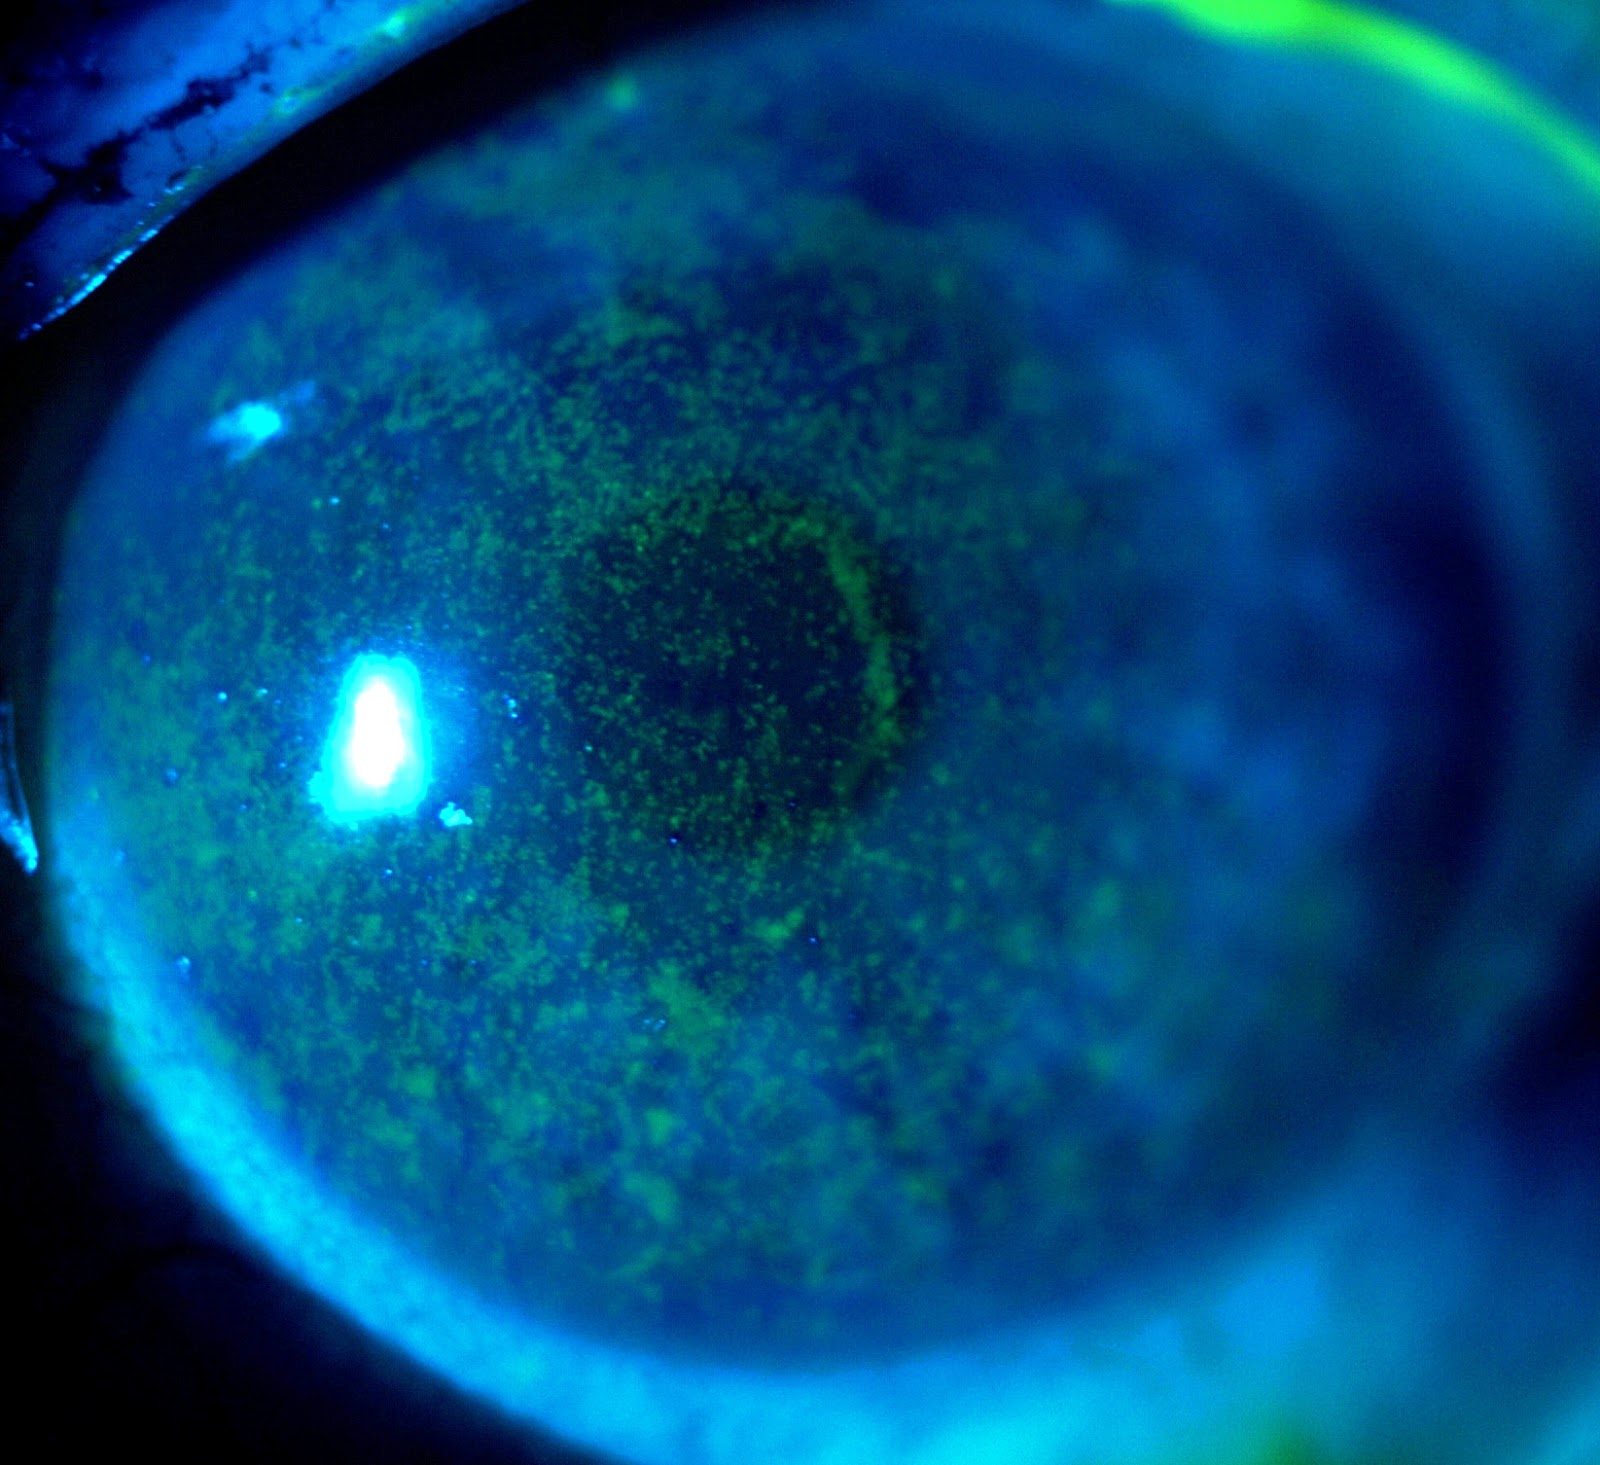

Kuru Goz Teshisi Icin Uygulanan Testler Gozdr Com Goz Sagligi Ve Hastaliklari

Goz Hastalik Test Kurugoz Istanbul Retina Enstitusu